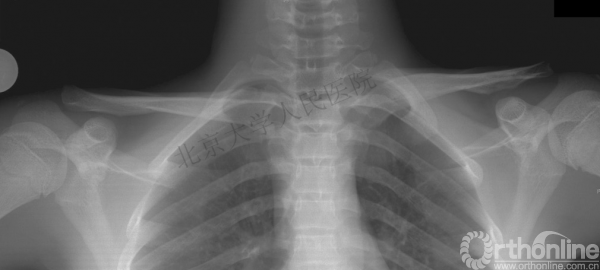

43岁男性,骑电动车时发生交通事故摔伤左肩及左胸

查体:左胸壁后方压痛;左锁骨近端区域凸起,压痛(+),远端未见明显畸形,压痛(+),锁骨轴向叩痛(+)

影像学检查—X线

你是否认为容易漏诊?